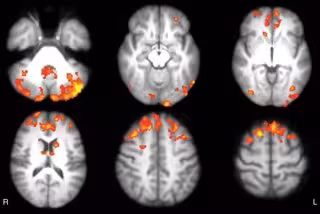

La imagen funcional cuando el cerebro está en estado de reposo o no se centra en una tarea en particular proporciona información importante sobre la conectividad neuronal. "La IRM funcional permite estudiar qué áreas del cerebro están activas simultáneamente y da información sobre la participación de ciertas áreas con circuitos específicos del cerebro --apunta De Giglio--. Cuando hablamos de una mayor conectividad, nos referimos a que estos circuitos se han modificado, elevando al mismo tiempo la extensión de las áreas que funcionan".

Durante el seguimiento, los 12 pacientes en el grupo de videojuegos tenían un aumento significativo en la conectividad funcional del tálamo en áreas del cerebro que corresponden al componente posterior de la red en modo estándar, que es una de las redes cerebrales más importantes implicadas en la cognición. Los resultados proporcionan un ejemplo de la plasticidad del cerebro, o la capacidad para formar nuevas conexiones a lo largo de la vida.

Las modificaciones en la conectividad funcional que se mostraron en el grupo de videojuegos después del entrenamiento correspondió a mejoras significativas en las puntuaciones de las pruebas que evalúan la atención y la función ejecutiva, habilidades cognitivas de nivel superior que ayudan a organizar nuestras vidas y regular nuestro comportamiento.